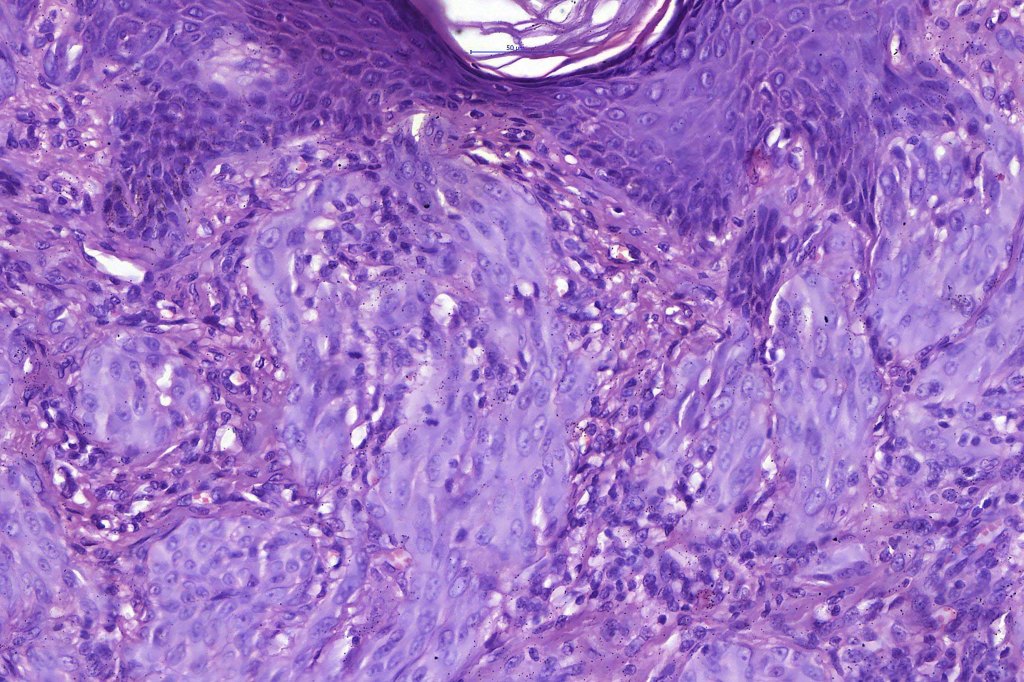

•Junctional nests often vertically orientated, dyscohesive with a surrounding retraction artifact

•Pleomorphism is almost invariable but affects all of the population to the same extent i.e., the cells & nuclei all look very much the same

•Spindle cell nests often display a “raining down” growth pattern

•Spindle cells have abundant cytoplasm and vesicular nuclei with small nucleoli

•Epithelioid cell variants often show greater pleomorphism and cells can frequently appear bizarre with abundant, sometimes ground glass cytoplasm and large vesicular nuclei with prominent eosinophilic nucleoli, multinucleate cells are often seen

•Intracytoplasmic pseudoinclusions commonly present in epithelioid cells

•Kamino bodies (often multiple) are a characteristic feature